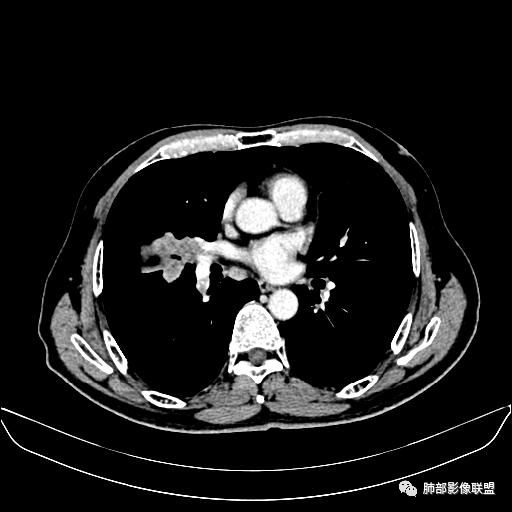

住院4天后行胸部增强CT

动脉期

老年男性,因“咳嗽咳痰1月余。”入院。病程中咳嗽咳痰,咳黄白痰,间断咯少许鲜红色痰血。PPD阳性。胸CT:右肺中叶外侧段支气管管腔阻塞,大片实性病变,病灶边缘光滑,部分边缘膨隆,可见分叶,肺门及纵隔可见肿大淋巴结,并可见钙化。增强可见病灶明显强化,而且延迟强化明显,病灶内多发低密度区,内见血管影,血管变细、部分血管破坏。考虑恶性病变可能性大,鉴别慢性肉芽肿性病变。

胸CT:跨叶大肿块,主体在中叶,右中叶外侧段支气管阻塞,病灶部分边缘膨隆,可见分叶,部分边缘平直,肺门及纵隔可见肿大淋巴结。增强病灶不均匀强化,延迟强化明显,病灶内多发低密度区,内见血管飘浮,部分血管变细、模糊。考虑:恶性病变可能性大,大细胞?淋巴瘤?鉴别慢性肉芽肿性病变。

右肺中叶软组织肿块,外围向内生长,叶间胸膜向前内移位,肿块近肺门侧跨叶,中叶外侧段支气管截断,密度不均匀,双侧肺门及隆突下见肿大淋巴结,增强后呈中度不均质强化,肺动脉供血,多发坏死区,边界尚清,坏死区域内见结构,结合病史考虑恶性,鉴别诊断1结核,爬行征是沿支气管树分布,外宽,内窄,周围有卫星灶,内气管狭窄后扩张,此例沿叶间胸膜长轴分布,气管有截断,不典型。2炎性肉芽肿,符合的地方下方层面增强后延迟性轻度环形强化,不符临床无发热等急性感染病史,实验室指标不符,病灶周围渗出及慢性炎性改变有,不明显。

吴婧老师和南边老师都对该病例进行了深入分析。从支气管管壁的增厚,支气管狭窄后扩张,支气管粘液栓,病灶形态,到病灶不均匀强化及坏死彻底,到周边病灶及肺组织空气的潴留,加之纵隔内淋巴结肿大伴钙化等等,都支持慢性炎性病灶,尤其是结核。

墨西哥仙人掌征---结核        影像上结核灶,粗大的均匀枝干,推测是支气管囊状扩张引起的,在非支气管区,形成圆形坏死囊群;如果这些坏死比较稀薄,又遇到扩张支气管,就会形成粗大的“墨西哥仙人掌”。结核引起的支气管近端炎症纤维化,可以造成支气管阻塞,从而将干酪样坏死物封堵在管腔内。仙人掌主干内部应该是干酪为主,稀薄的,具有流动性,时间久了会出现钙化。

结核坏死与鳞癌鉴别有一点是结核坏死没有方向性,鳞癌有。鳞癌靠近支气管近端部分,血供容易维持,不易坏死,所以坏死靠外侧。而结核干酪样坏死,把一定体积的流动性坏死物,包裹起来,什么形状最省料?坏死物包裹,表面积最省的自然是圆球形,而遇到支气管,坏死物一多,就把支气管撑大了。包裹物是就地取材,扩张的支气管就成了包裹结构。